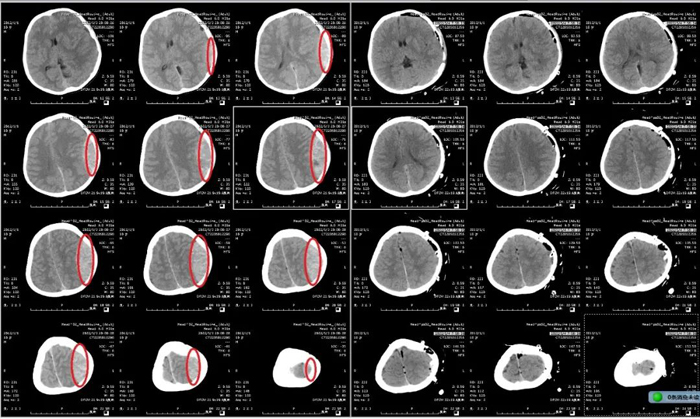

患兒,男,9歲,因“摔傷頭部后神志喪失1小時余”由120送到我院急診搶救室就診。入院時患兒昏迷、病危狀態,不能言語,一側瞳孔散大固定,伴一側肢體偏癱。急診顱腦CT檢查提示:左側巨大顱內血腫,中線移位。急診神經外科當值醫師及上級醫師綜合評估病情后,決定立即啟動急診綠色通道。

時間就是生命,對于神經急危重癥患者,每一秒鐘對于整個疾病的搶救過程都彌足珍貴。呂守華主任接到電話后第一時間來到醫院,臨場組織搶救,指導手術。手術者蓋大偉主治醫師以精湛的技術用時100分鐘順利完成手術,術后復查示顱內血腫清除滿意。

顱腦CT術前、術后對比